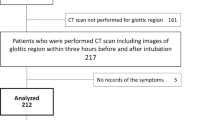

The flow chart of the study is shown in Fig. 2. Eight infants were excluded due to censored data (4 cases of censored pneumonia data and 4 cases of censored throat area data). Finally, 96 infants were included in the study, among whom 29 were level I difficulty, 43 were level II difficulty, and 24 were level III difficulty of tracheal intubation. Additional data with sufficient clinical information were collected.